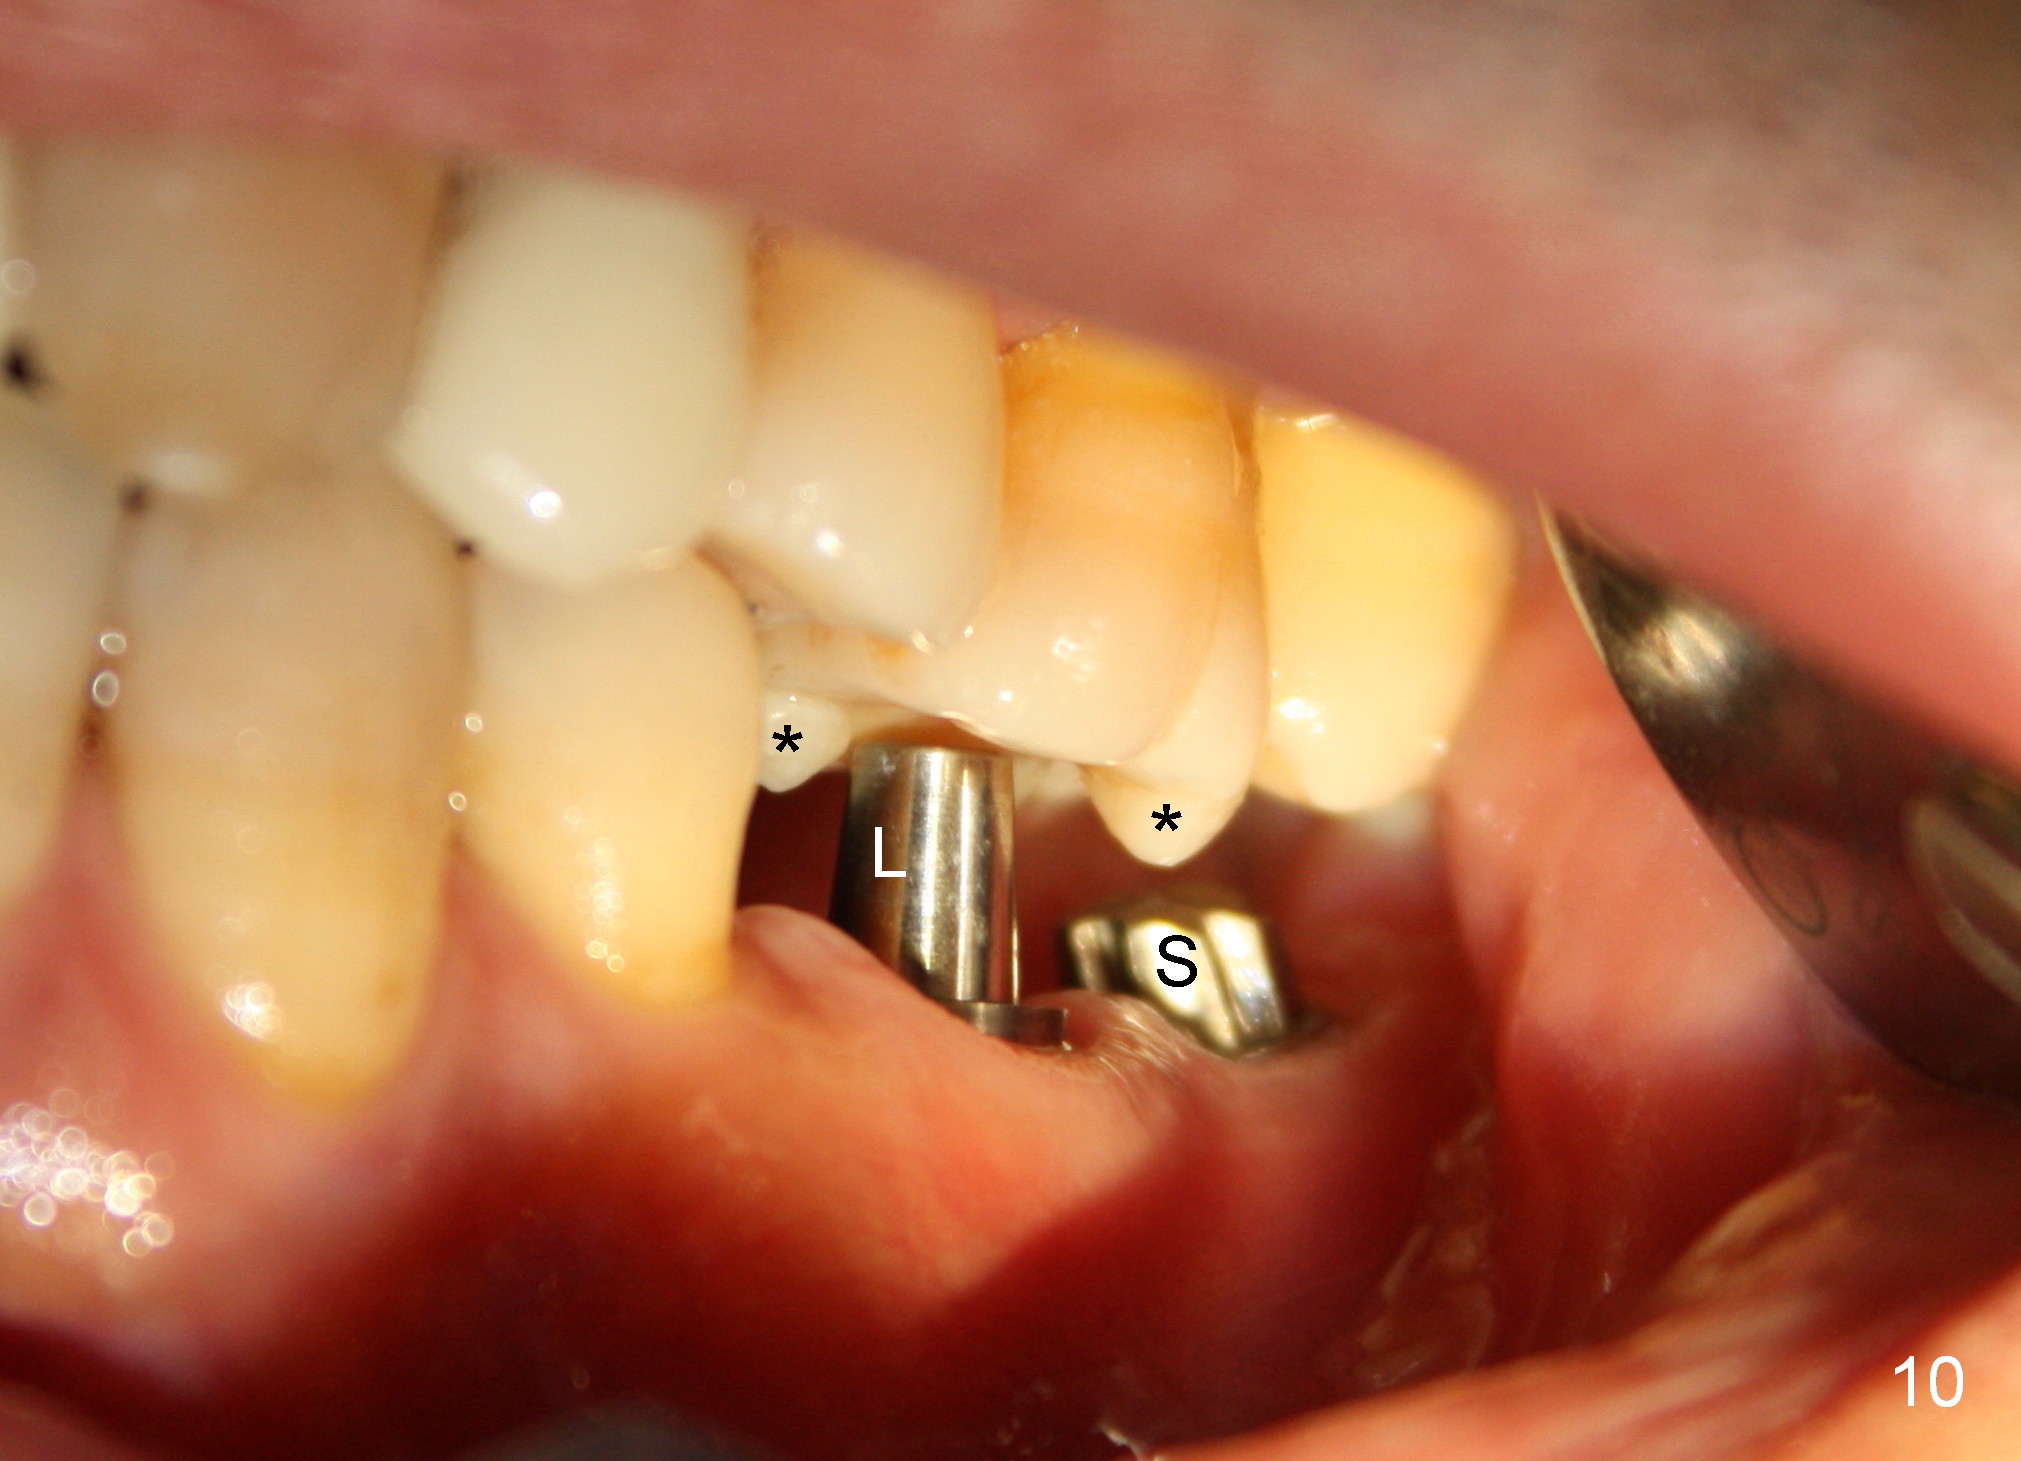

A 41-year-old man has chronic periodontits with bruxism. The teeth #14 and 15 are supraerupted (Fig.1 arrows) with furcal lesion (Fig.2 (CT) *). These 2 molars have guarded to poor prognosis. Due to insurance benefit limitation, we plan to save them temporarily with periodontal surgery so that bone loss would not get worse when the teeth are being intruded. After opposing implant placement (Fig.3), flaps are raised to remove calculus and granulation tissue (Fig.4, no bone graft). Twenty days later, three mini-implants are placed (Fig.5,6). The implant distopalatal to #15 is loose nearly 2 months postop (Fig.7 *) and retightened. The following month the same implant is placed higher for stability (Fig.8). The Intrusion takes <5.5 months (Fig.9,10).